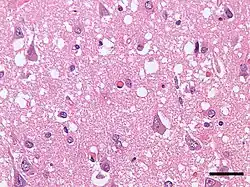

| Micrograph showing spongiform degeneration (vacuoles that appear as holes in tissue sections) in the cerebral cortex of a patient who had died of Creutzfeldt–Jakob disease. H&E stain, scale bar = 30 microns (0.03 mm). | |

Prion diseases are marked by mental and physical deterioration that worsens over time.[5][6] A defining pathologic characteristic of prion diseases is the appearance of small vacuoles in various parts of the central nervous system that create a sponge-like appearance when brain tissue obtained at autopsy is examined under a microscope.[2][3] Other changes in affected regions include the buildup of PrPSc, gliosis, and the loss of neurons.[7]